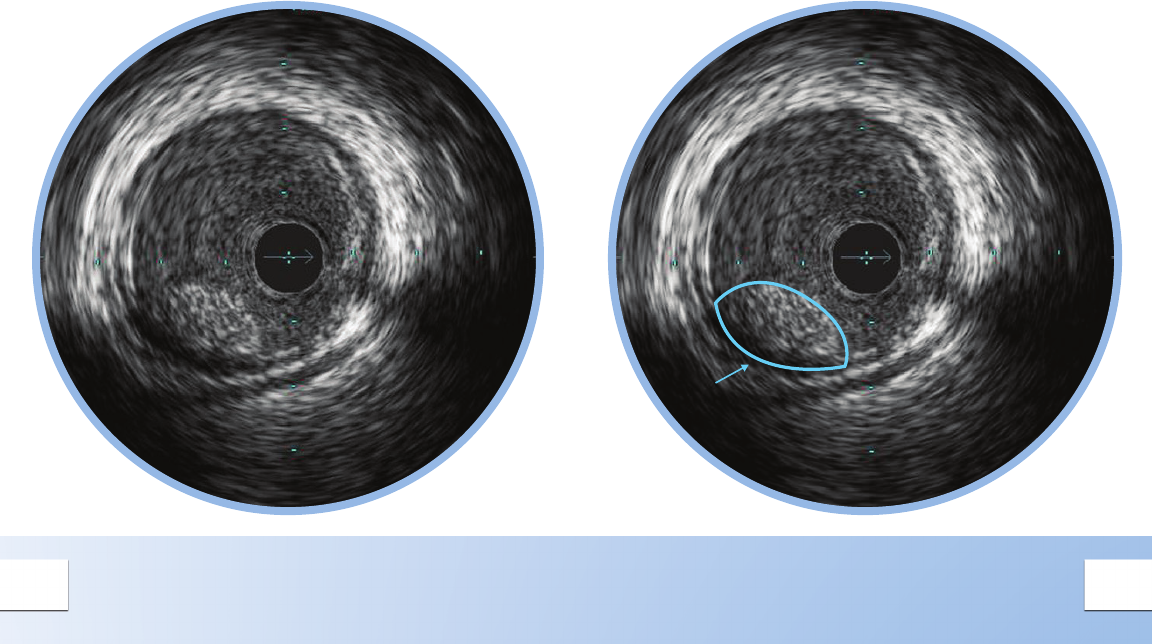

ECCENTRIC MIXED PLAQUE

Eccentric plaques are distributed non-

circumferentially in the vessel; this makes the

assessment of disease by angiography especially

prone to underestimation or overestimation

depending on the angle of view.

Calcium is indicated by very bright areas with

acoustic shadowing that blocks out the image

behind. This shadowing occurs because the high

density of calcium dampens the ultrasound echo.

Nearby vessels on the periphery can be seen

moving in and out of the eld of view and can be

used as landmarks.